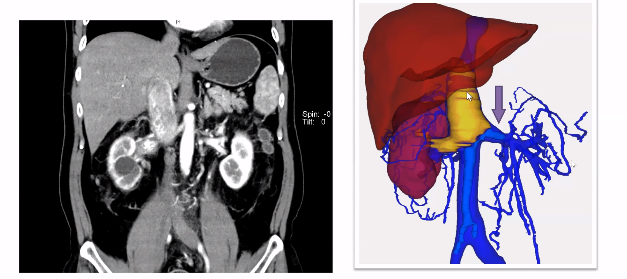

既往手术切除肾脏我们通常都会先处理肾动脉,但事实上有相当一部分患者可以先切断下腔静脉,再处理肾动脉,这样的病例在临床中也比较常见。如下图所示,当患者瘤栓充满血栓后,没有很好的空间去寻找肾动脉,此时我们可以先离断下腔静脉,这样就有足够的空间,再去取瘤栓和切断肾动脉就会变得简单便捷。当前这种模式本科室也已成为一种常规的术式,通过这种方式可以简化手术步骤,同时也可以很好地处理掉肾动脉。

如下图所示,该病例瘤栓充满整个下腔静脉,同时长满血栓,对于该病例我们采用全封闭式的En-block切除,首先是离断下腔静脉,翻起来以后去找寻右肾动脉,切断右肾动脉以后再把左肾静脉切断,然后一直沿着瘤栓向肝后寻找游离肝门后方腔静脉。既往类似病例中肝门后方腔静脉很难暴露清楚,但是有了机器人助力,使其充分显露出来就变的相对容易很多。肝后下腔静脉经过充分游离后,再将瘤栓全部挤压进入腔静脉中,然后探查至无瘤栓处,直线切断腔静脉,将瘤栓取出。完全封闭式的瘤栓取出,可以获得很好的操作空间。该病例曾在2023年4月在第8届泌尿生殖系统研讨会上进行演示。